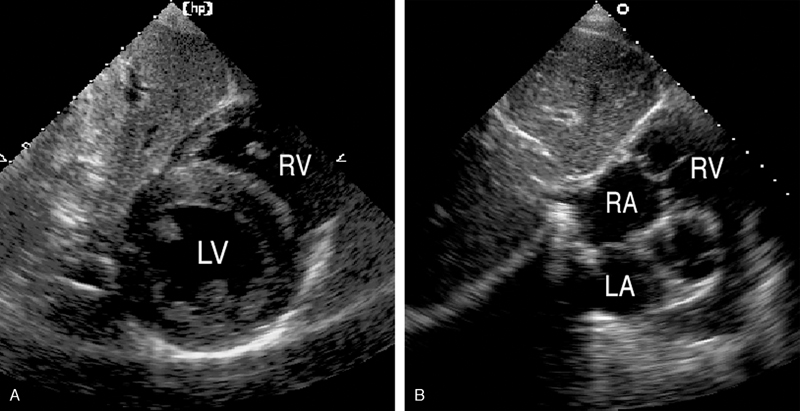

فحوصات تشخيصية لبعض امراض القلب والشرايين التاجية